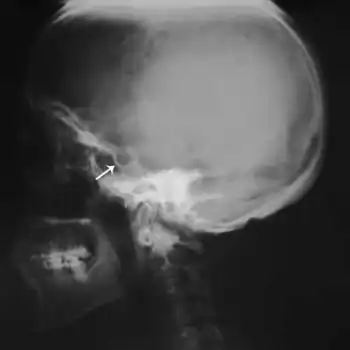

An individual with Mulibrey nanism has growth retardation, a short broad neck, misshapen sternum, small thorax, square shoulders, enlarged liver, and yellowish dots in the ocular fundi.[1][7][8] Individuals with Mulibrey nanism have also been reported to have intellectual disability, tumors, and infertility.[1]